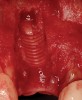

The chief complaint of a 48-year-old woman who presented to her restorative dentist was, “I don’t like the way my implant looks” (Figure 1). This implant had been placed by a previous periodontist and restorative dentist. The patient is now seeking a second opinion. In evaluating this case upon referral to the periodontist, a reddened appearance of the gingival and mucosal tissue encompassing almost the entire facial aspect could be observed. In addition, the radiographs demonstrated a 5-mm diameter implant in place with a deciduous cuspid in the place of No. 11. Deep probing depths were noted around the facial aspect of the implant, and threads could be detected under the tissue.

In evaluating the options, it was decided that the implant placed was too large and that the deciduous cuspid site could be used for a single implant as an abutment for a cantilevered pontic to restore the missing lateral incisor in a more esthetic manner. The goal the treatment was to augment the lateral incisor site in order to bring the facial tissue level more coronal (Figure 2 through Figure 11).